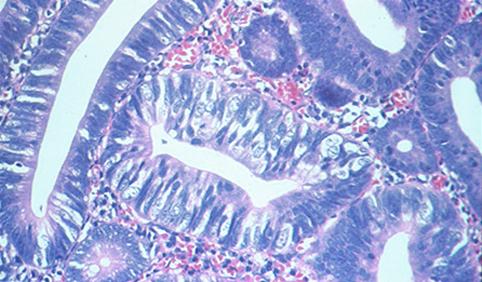

Criteria of Hist.ClassificationMalignant epithelial tumor/Adenocarcinoma

LocationLarge intestine(Colon)/Descending colon

Technique, MethodHistology

Macroscopic TypesType 0/I (Is) Sessile type

Size20 - 24

Depth of Tumor Invasionmucosa